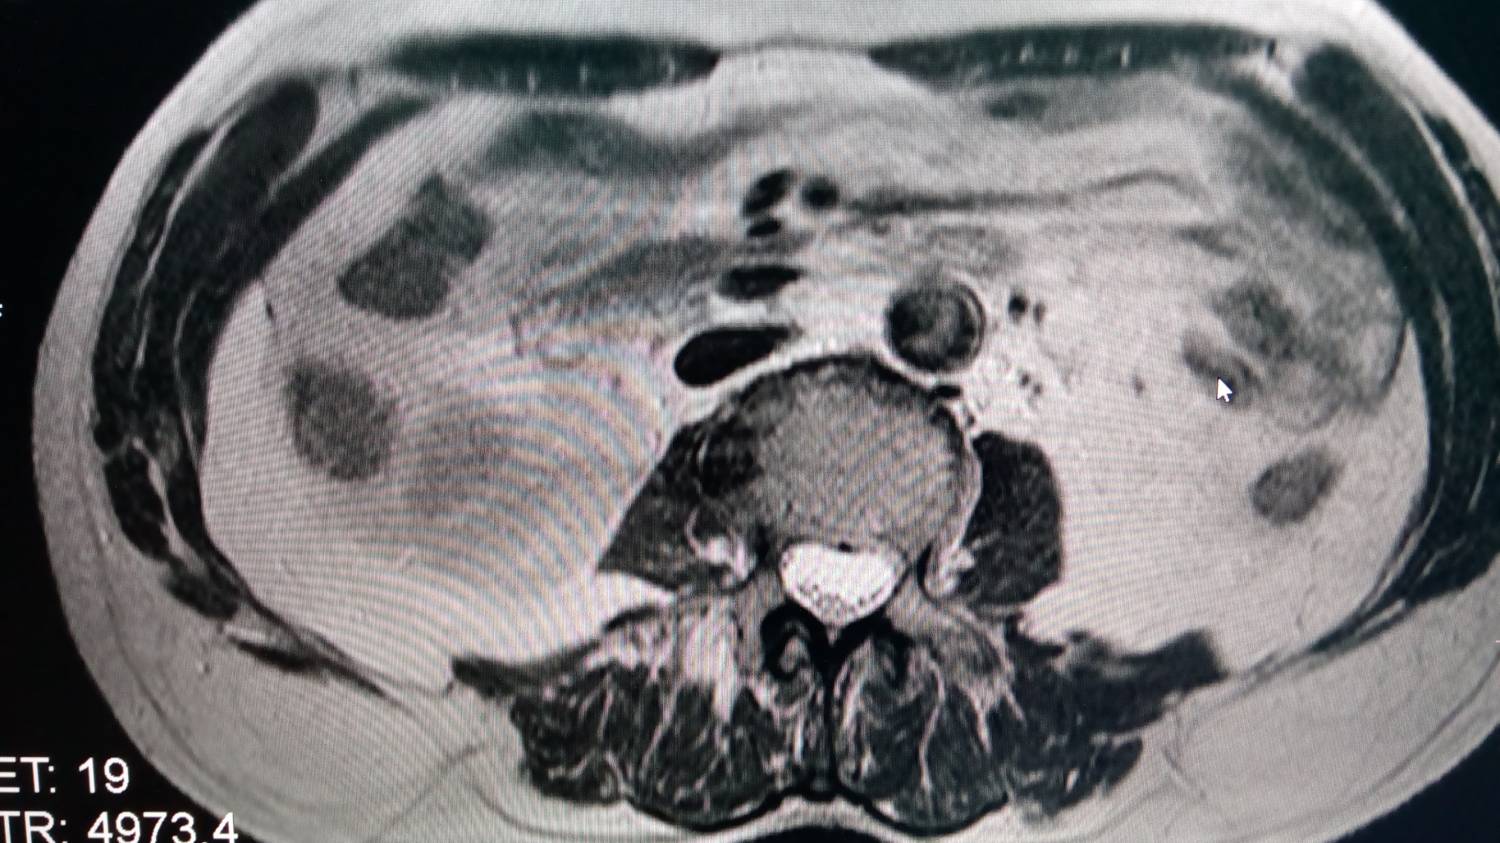

Периодически по непонятной причине на снимках появляются артефакты типа "ковер", снимки прилагаю,причем снимки находятся в одной серии - идет нормальный, следующий с ковром и потом опять нормальный, а также некорректно работает программа подавления жира.

7696509.jpg (135.8 Kb) · 7036744.jpg (154.2 Kb)